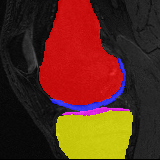

Moving Target Mono-0 Mono-5 DA-1 DA-5 Mono-200 Refer to caption Refer to caption Refer to caption Refer to caption Refer to caption Refer to caption Refer to caption Refer to caption Refer to caption Refer to caption Refer to caption Refer to caption Refer to caption Refer to caption

Figure 2:  Examples of knee MRI registration (top) and brain MRI segmentation (bottom) results. Top: The first two columns are the moving image/segmentation and the target image/segmentation followed by the warped moving images (with deformation grids)/segmentations by different models. Bottom left to right: original image, manual segmentation, and predictions of various models. Mono-i𝑖i and DA-i𝑖i represent the mono- and DA models with i𝑖i manual segmentations respectively.

Moving Target Mono-0 Mono-21 DA-1 DA-21 Mono-65 Refer to caption Refer to caption Refer to caption Refer to caption Refer to caption Refer to caption Refer to caption Refer to caption Refer to caption Refer to caption Refer to caption Refer to caption Refer to caption Refer to caption

Figure 4: Examples of brain MRI registration (top) and knee MRI segmentation (bottom) results. Top: The first two columns are the moving image/segmentation and the target image/segmentation followed by the warped moving images/segmentations by different models. Bottom left to right: original image, manual segmentation, and predictions of various models. Mono-i𝑖i and DA-i𝑖i represent the mono- and DA models trained with i𝑖i manual segmentations respectively.